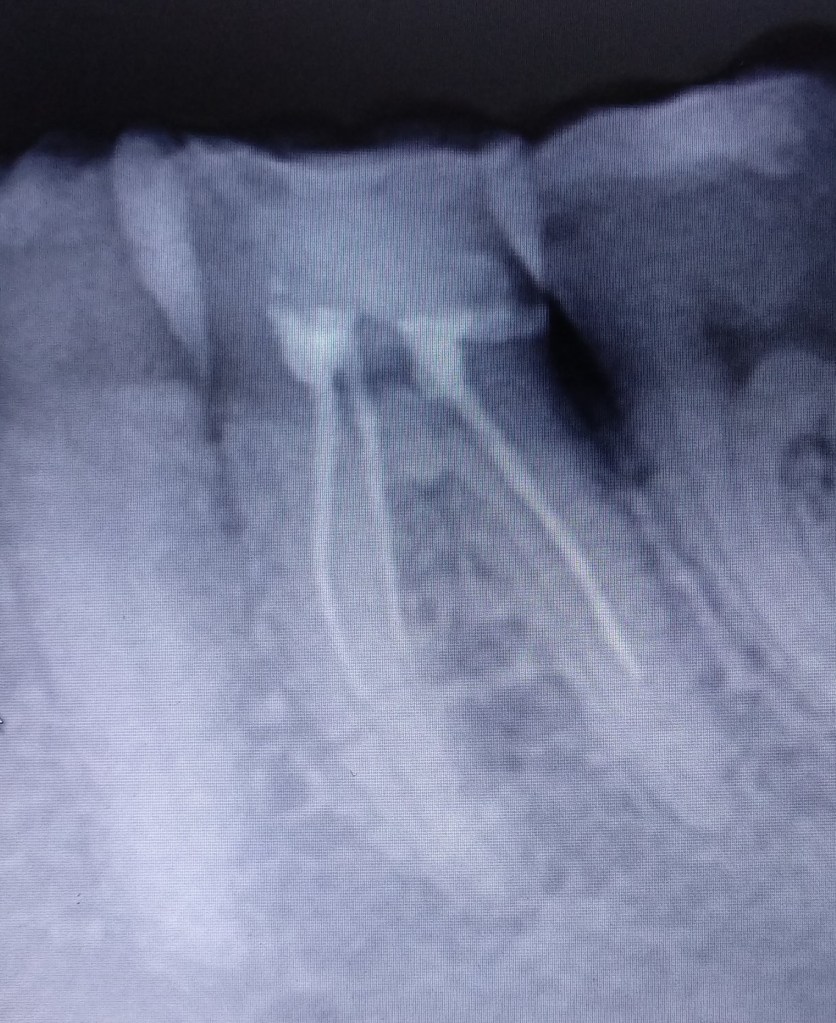

Gyökértömés cseréje: pontatlan (nem csúcsig érő, nem falálló) gyökértömések cseréje

Megmunkálás: gépi gyökércsatorna tágító (Reciproc)

Munkahossz meghatározása: apex locator (EndoPilot).

Nagyítás típusa: operációs mikroszkóp (25×)